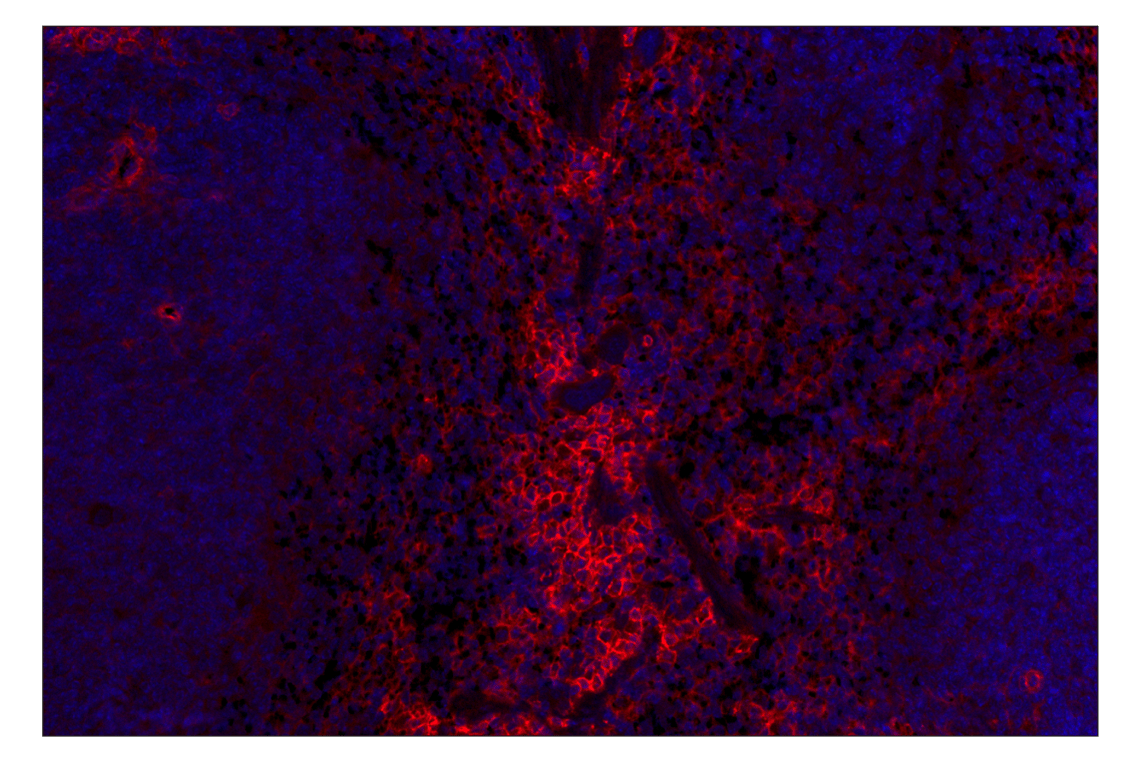

CD39/NTPDase 1 (E2X6B) Rabbit Monoclonal Antibody (Alexa Fluor® 647 Conjugate) #77399

This Cell Signaling Technology® antibody is conjugated to Alexa Fluor® 647 fluorescent dye under optimal conditions. This antibody conjugate is expected to exhibit the same species cross-reactivity as the unconjugated CD39/NTPDase 1 (E2X6B) Rabbit mAb #14481.

Immunohistochemistry (Paraffin) 1:100 - 1:400

CD39/NTPDase 1 (E2X6B) Rabbit Monoclonal Antibody (Alexa Fluor® 647 Conjugate) recognizes endogenous levels of total NTPDase 1 protein.

Monoclonal antibody is produced by immunizing animals with a synthetic peptide corresponding to residues surrounding Lys307 of mouse NTPDase 1 protein.